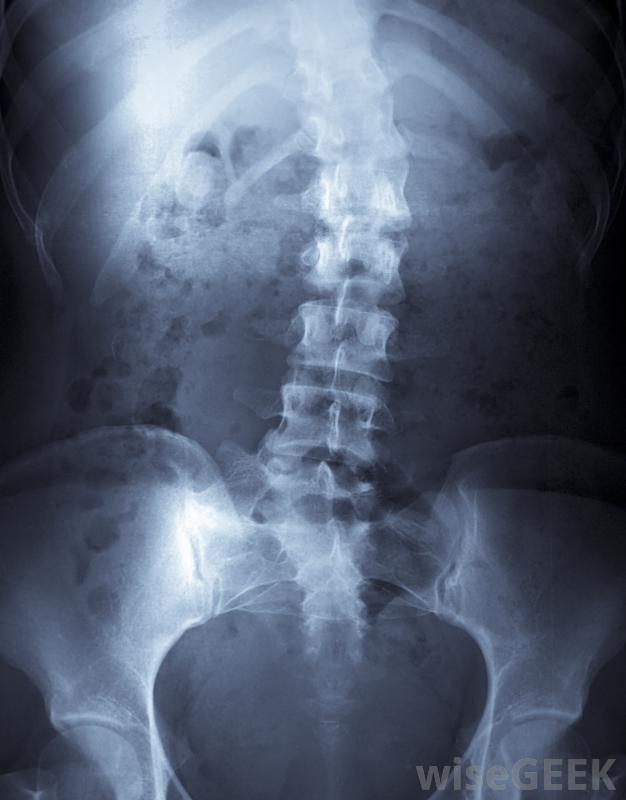

侏儒癥,可能導致脊柱畸形,如脊柱側凸。

發育不全是由骨和軟骨發育問題引起的另一種不成比例的侏儒癥畸形發育不良導致手臂和腿明顯縮短,脊柱畸形如脊柱側凸,以及關節活動障礙。大約一半的兒童先天性腭裂,耳朵畸形很常見。智力不受影響,但是患有先天性發育不良的人通常會有行動能力和運動控制方面的問題。這種疾病類似于一種叫做骨發育不全的疾病,2型,但后者嚴重得多,會導致嬰兒死產或死亡。